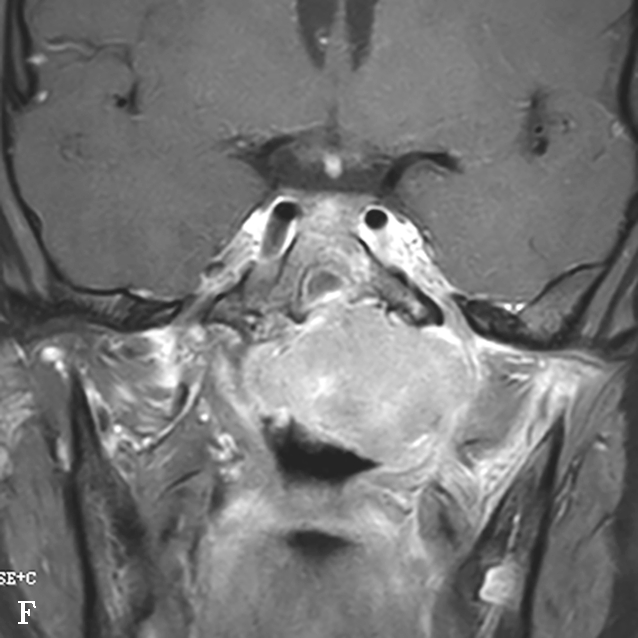

图1-2-5 青少年非角化型鼻咽癌

患者男,14岁,反复间断鼻出血、头晕头痛20余天。A.鼻窦CT横断面骨窗,示鼻咽顶后壁左侧软组织肿块,累及后鼻孔区,邻近左侧岩尖、蝶骨翼突骨质破坏、不完整,边缘毛糙;B.鼻窦CT冠状面重组骨窗,示左侧鼻咽顶后壁软组织肿块,邻近蝶骨翼突溶骨性骨质破坏,累及蝶骨体,边缘毛糙不整;C.鼻咽部MR T 2 WI横断面,示鼻咽左侧壁软组织肿块呈不均匀稍高信号,其间可见条状高信号,未见血管流空影;病变累及左侧翼内肌、窦后脂肪间隙;左侧上颌窦内可见积液呈明显高信号;D.鼻咽部MR T 1 WI横断面,示鼻咽部软组织肿块呈等信号,左侧上颌窦内积液呈低信号;E.鼻咽部MR T 1 WI横断面增强脂肪抑制序列,示鼻咽部病变呈明显强化,累及鼻咽左侧壁、顶后壁并跨越中线累及右侧咽隐窝,右侧咽后间隙淋巴结可见,与软组织肿块同步强化;F.鼻咽部MR T 1 WI冠状面增强脂肪抑制序列,示病变累及左侧咽旁间隙,左侧上颌神经明显增粗强化,并经上颌神经累及左侧海绵窦致其增厚、强化。活检病理符合鼻咽癌(非角化型)